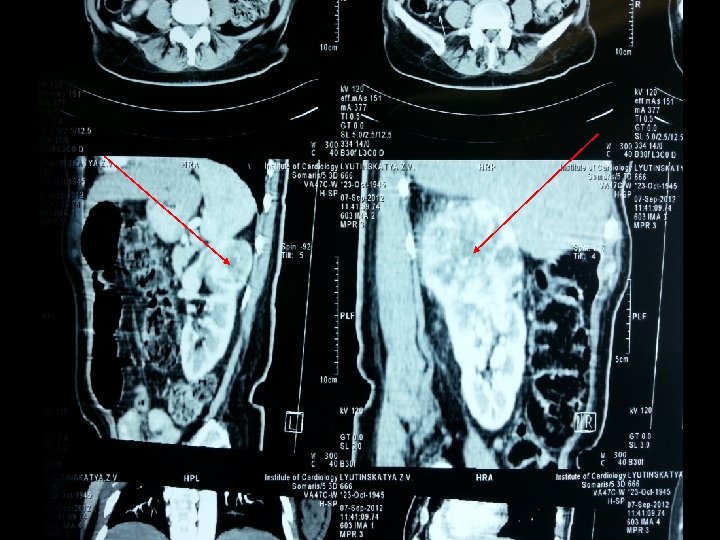

УЗИ • Новообразование левой почки • Новообразование правой почки КТ Обнаружены новообразования в верхних полюсах обеих почек Лимфаденопатии и асцита не выявлено